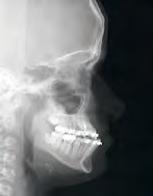

RESULTADOS NOTABLES

Radiografía Clase III

Antes

Después

Imágenes cedidas a Dynaflex por el Dr. Andy Hayes de St. Louis MO